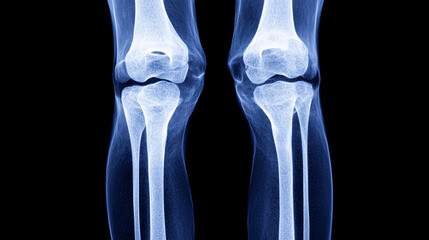

Podobny obraz Medical Elbow Anterior View X-Ray Radiograph Illustrating...